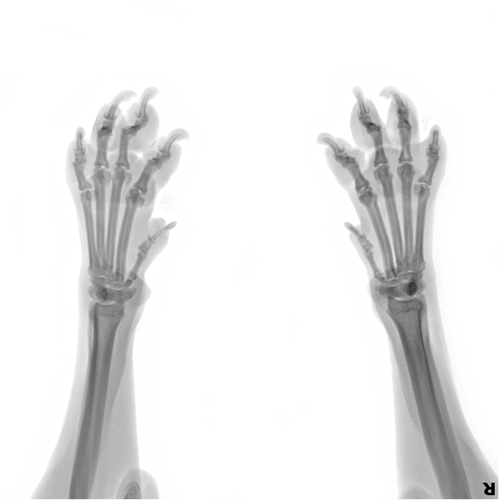

Рентген лап

Диагностическая процедура используется для оценки костной ткани и других структур в лапах собаки. Оно может быть полезным при диагностике переломов, артрита, остеохондроза, опухолей и других патологий.